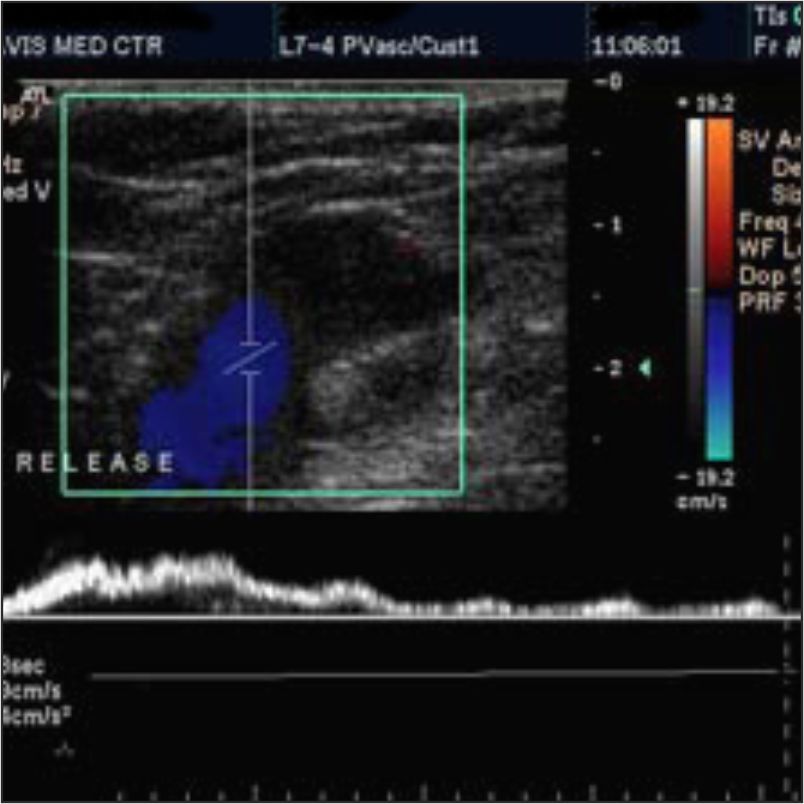

Color Doppler. By using a computer this test converts sound waves into different colors. These different colors show the speed and direction of blood flow in real-time.

Spectral Doppler. This test shows blood flow information on a graph rather than colored images. This helps to show how much of the blood vessel is blocked.

Duplex Doppler. This test uses standard ultrasound to take pictures of blood vessels and organs. The computer then converts the images into a graph, as in the Spectral Doppler.